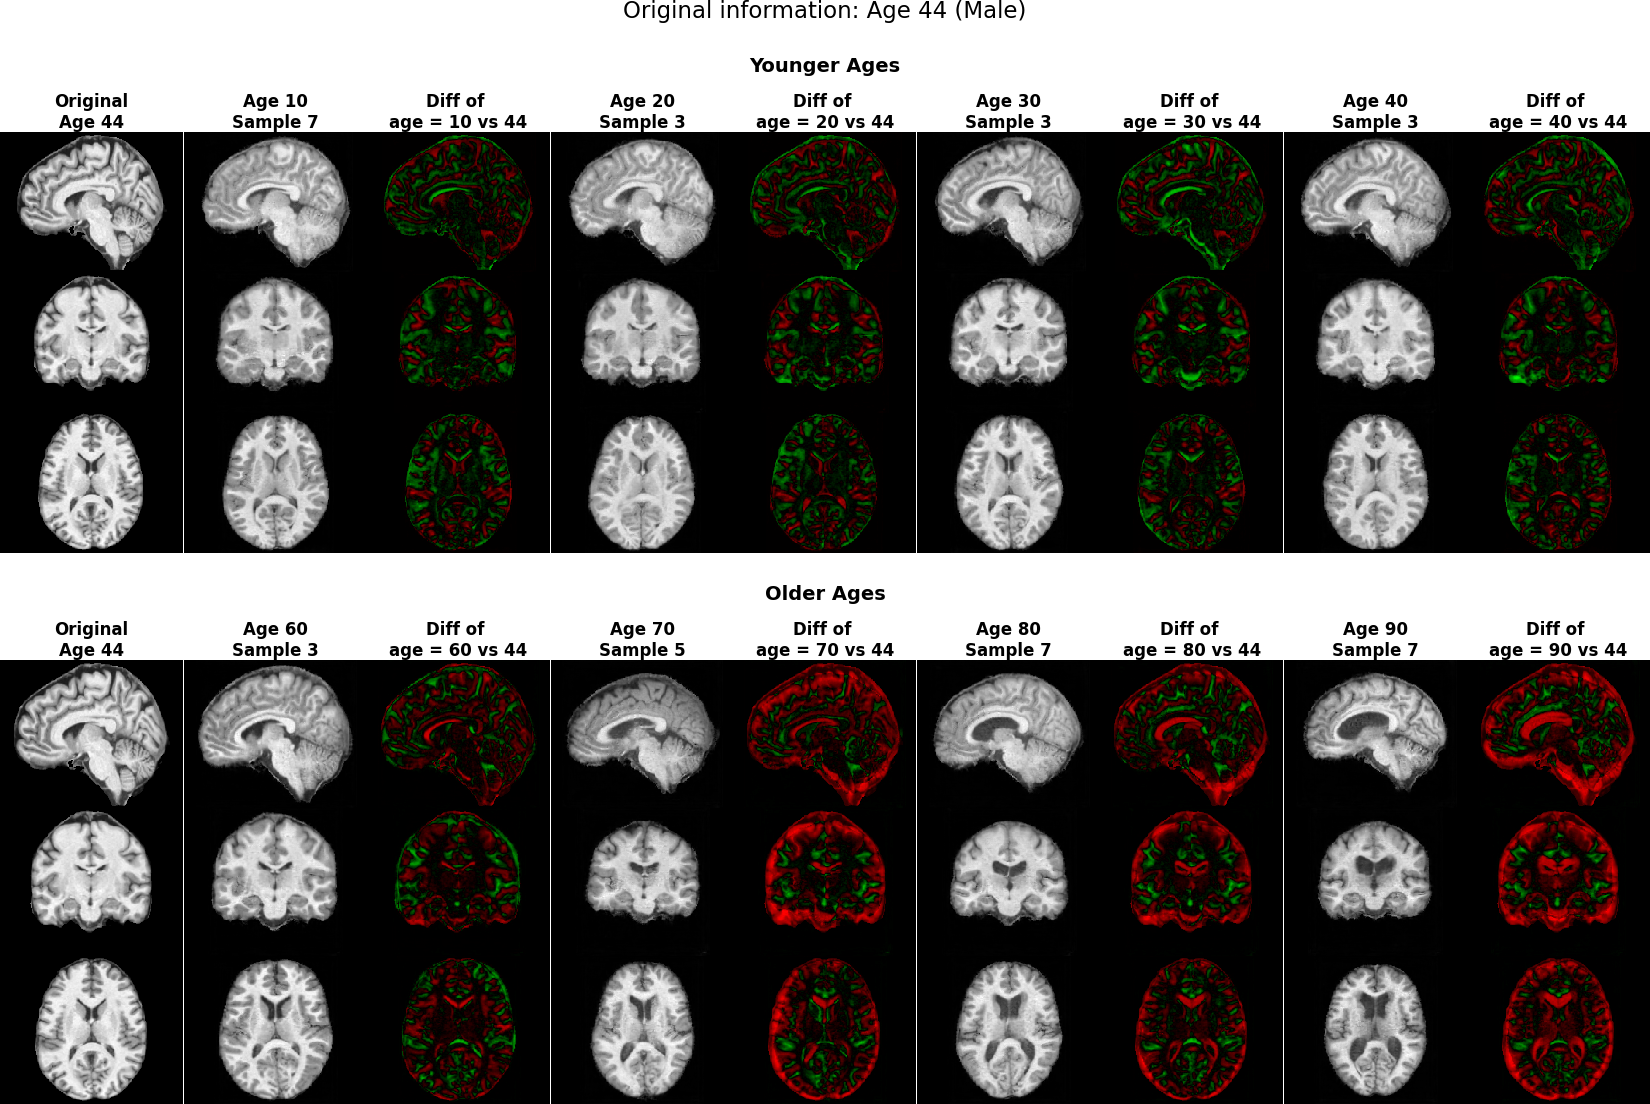

Brain MRIs Figure 5 showcases the generated brain MRI images conditioned on a 65-year-old male individual. Unlike younger age groups (e.g. 10-20 years old) with characteristic small ventricles, or the older age groups (e.g. 70+ years old) with large ventricles alasar2019morphometric; 10.1001/jamanetworkopen.2023.18153; 10.1001/archneur.60.7.989, the 60s age range includes a wide variety of ventricle patterns raz2004aging, as visualized in Figure 5a with actual samples. While all models generated high-quality images, Rainbow effectively captures the diverse ventricle patterns with varying ventricle sizes, whereas the baseline LDM tends to produce similar ventricle regions across different samples. We provide full axial, coronal, and sagittal views for this experiment in Figure 28 and visibility of structures and details in generated 3D MRIs in Figure 27 in Appendix E.

In addition, we quantify brain MRI generations obtained from multiple tasks: image synthesis (with 200 conditions balanced on age and sex) and counterfactuals on age (three age shifts at 10, 40, and 80 years) and sex (flipping binary sex). For each task, we report FID score Seitzer2020FID and performance on age and sex prediction by pretrained classifier models (details at Appendix D.2). As shown in Table 1, Rainbow outperforms LDM and GAN baselines across all metrics and tasks with lower FID, higher sex accuracy, and lower age MAE. To justify age and sex prediction models, we report "Real" results that were tested on real data and "Random" results that were evaluated on random outputs. Figure 29 in Appendix E provides counterfactual generations.

For brain MRI, we perform a counterfactual generation task. Given the factual image and condition, the task is to generate a counterfactual MRI based on a counterfactual condition on age or sex. Table 1 presents the numerical evaluation of the classification of sex and age based on the generated counterfactuals. Rainbow achieves higher performance, which underscores its effectiveness. Figure 29 compares the counterfactual generations. Both Rainbow and LDM generate correct patterns, such as smaller ventricles at a younger age (do(age=10)), evident from the red regions in the difference plot, and larger ventricles and cortex at an older age (do(age=80)), shown by the green regions. Additionally, sex conversion from male to female shows smaller ventricles and partially larger cortex regions. However, the baseline LDM exhibits some artifacts. These findings are consistent with previous studies on the effects of age and sex on MRI characteristics [fjell2009minute, gur1995sex, Xu112].